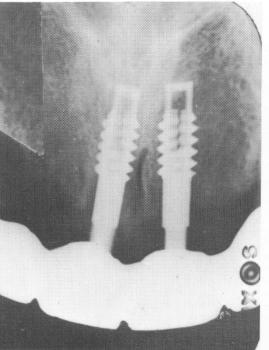

then fastened to the mesostructure with the obliquely directed set screws. The bite was once again balanced (Fig. 10-203), and a postoperative radio-graph of the implants was taken (Fig. 10-204).

Fig. 10-204. An intraoral radiograph reveals the two inter nally threaded vent-plants.

1 Intraoral radiograph reveals two internally threaded ventplants